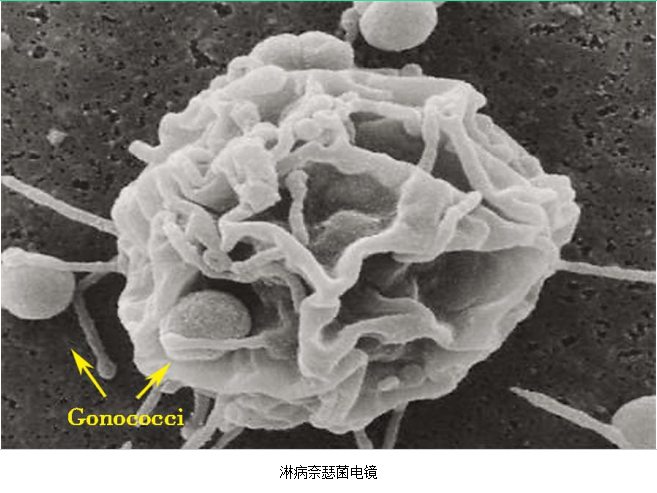

急性子宫颈炎的病原体:①性传播疾病病原体:淋病奈瑟菌及沙眼衣原体,主要见于性传播疾病的高危人群;②内源性病原体:部分子宫颈炎的病原体与细菌性阴道病病原体、生殖支原体感染有关。但也有部分患者的病原体不清楚。沙眼衣原体及淋病奈瑟菌均感染子宫颈管柱状上皮,沿黏膜面扩散引起浅层感染,病变以子宫颈管明显。除子宫颈管柱状上皮外,淋病奈瑟菌还常侵袭尿道移行上皮、尿道旁腺及前庭大腺。

3.病原体检测 应作衣原体及淋病奈瑟菌的检测,以及有无细菌性阴道病及滴虫阴道炎。检测淋病奈瑟菌常用的方法有:①分泌物涂片革兰染色,查找中性粒细胞内有无革兰阴性双球菌,由于子宫颈分泌物的敏感性、特异性差,不推荐用于女性淋病的诊断方法。②淋病奈瑟菌培养,为诊断淋病的金标准方法。③核酸检测,包括核酸杂交及核酸扩增,尤其核酸扩增方法诊断淋病奈瑟菌感染的敏感性及特异性高。检测沙眼衣原体常用的方法有:①衣原体培养,因其方法复杂,临床少用。②酶联免疫吸附试验检测沙眼衣原体抗原,为临床常用的方法。③核酸检测,包括核酸杂交及核酸扩增,尤以后者为检测衣原体感染敏感、特异的方法。但应做好质量控制,避免污染。